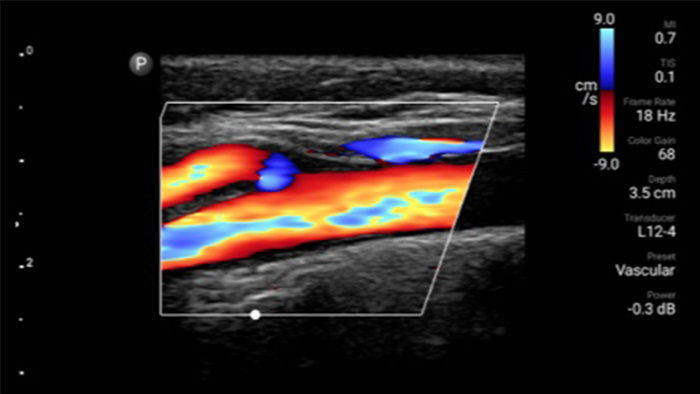

Lumify kan helpen de subtiele details van een beeld zichtbaar te maken en afwijkende weefselstructuren bloot te leggen vanuit verschillende hoeken. Hierdoor kunt u met vertrouwen realtime beslissingen nemen, van diagnose tot herstel.